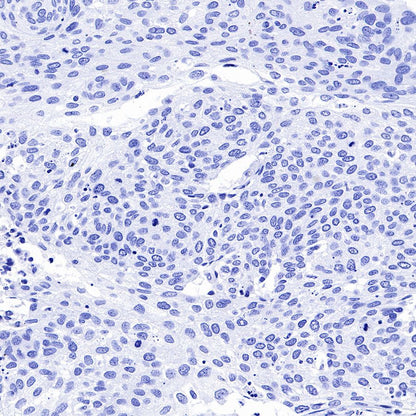

Negative control: IHC shows negative staining in paraffin-embedded human breast cancer. Anti-GPA33 antibody was used at 1/2000 dilution, followed by a HRP Polymer for Mouse & Rabbit IgG (ready to use). Counterstained with hematoxylin. Heat mediated antigen retrieval with Tris/EDTA buffer pH9.0 was performed before commencing with IHC staining protocol.